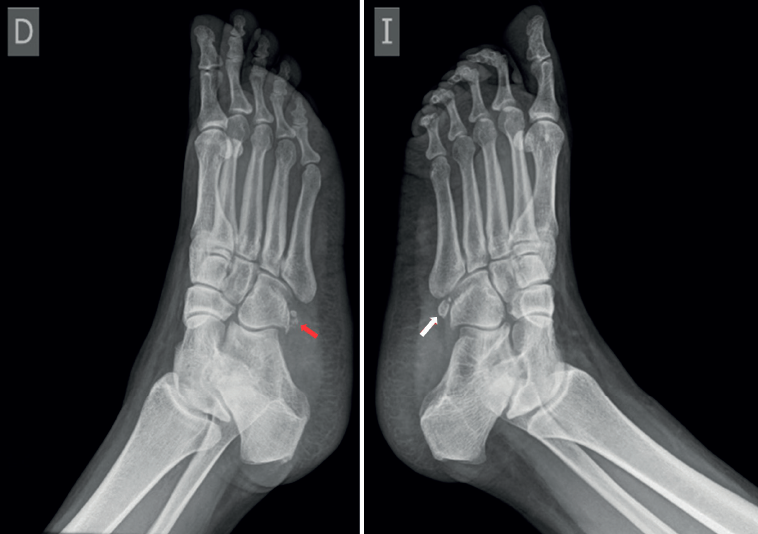

En el caso presentado se sospechó radiográficamente fractura del hueso cuboides, por lo que se indicó TC que informó fractura no desplazada de OP. El uso combinado de radiografías bilaterales (Figura 4) y TC (Figura 2) permitió diferenciar la presencia de variantes anatómicas como el OP, además de distinguir un OP bipartito de una fractura de este.

Se realizaron radiografías bilaterales del pie que evidenciaron la presencia de OP bilateral, con irregularidad en el margen del OP derecho. Inicialmente, se sospechó fractura del hueso cuboides (Figura 1); sin embargo, una tomografía computarizada (TC) descartó dicha fractura e identificó un trazo de fractura en el OP derecho, sin desplazamiento (Figura 2). Se realizó resonancia magnética (RM) del pie derecho que confirmó edema en OP del TPL, no desplazada ni complicada. TPL íntegro.